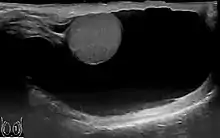

Scrotal ultrasound of a 10 cm large hydrocele, with anechoic (dark) fluid surrounding the testicle

The swelling is soft and non-tender, large in size on examination, and the testis cannot usually be felt. The presence of fluid is demonstrated by transillumination. These hydroceles can reach a huge size, containing large amount of fluid, as these are painless and are often ignored. They are otherwise asymptomatic, other than size and weight, causing inconvenience. However the long continued presence of large hydroceles causes atrophy of testis due to compression or by obstructing blood supply. In most cases, the hydrocele, when diagnosed early during complete physical examination, are small and the testis can easily be palpated within a lax hydrocele. However Ultrasound imaging is necessary to visualize the testis if the hydrocele sac is dense to reveal the primary abnormality. But these can become large in cases when left unattended. Hydroceles are usually painless, as are testicular tumors. A common method of diagnosing a hydrocele is by attempting to shine a strong light (transillumination) through the enlarged scrotum. A hydrocele will usually pass light, while a tumor will not (except in the case of a malignancy with reactive hydrocele).